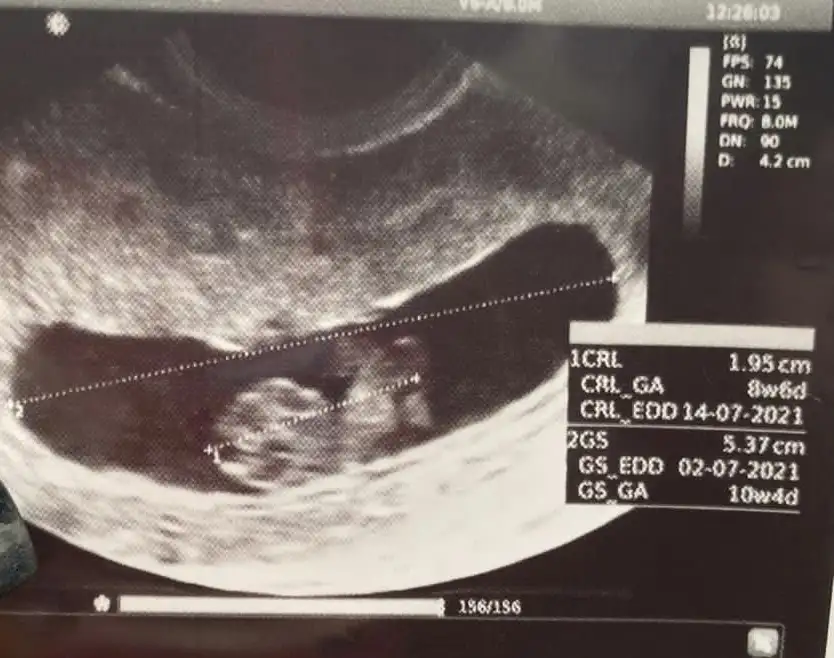

Bende 12 haftalık hamileyim cinsiyetini merak ediyorum banada bakarmısınız

merhabalar banada yorum yapabilirmisiniz foto 12+4 tü şuan 15. haftadayım 2 oğlum var bu 3 cü olacak inşallah cinsiyetini çok merak ediyorum rabbim ilk önce sağlık versin